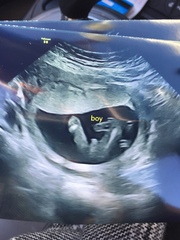

Even though we already new it was a boy we had our 20week scan today everythig is okay and defo a little boy!!! Im a bit confussed when my next midwife appointment should be as I havent had one since 15weeks and no letters about future ones either and im 20+3

@Lulabell1 - lovely scan pic, congrats on your boy 😍